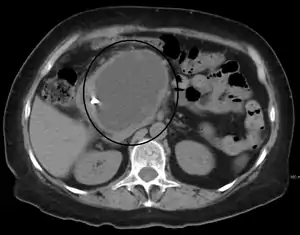

| A pancreatic pseudocyst as seen on CT | |

- Computerized tomography[10] – this is the gold standard for initial assessment and follow-up.